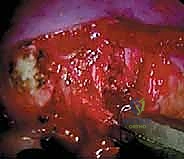

الخطوة الثالثة: الدخول إلى تجويف الصدر وإفراغ الرئة

يتم إدخال الكاميرا، وتظهر الصورة بدقة 4K على الشاشات الكبيرة في غرفة العمليات. يتم إفراغ الرئة بالكامل (Lung deflation)، مما يكشف عن التشريح الداخلي للصدر: العمود الفقري، الأضلاع، الشريان الأورطي (أو الوريد الأجوف حسب الجانب)، والسلسلة العصبية الودية.